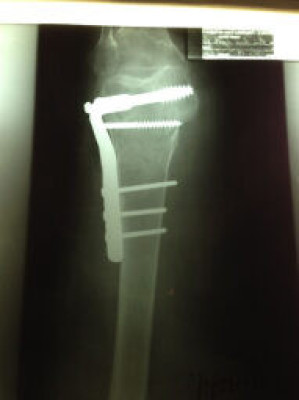

Fractura de Cadera